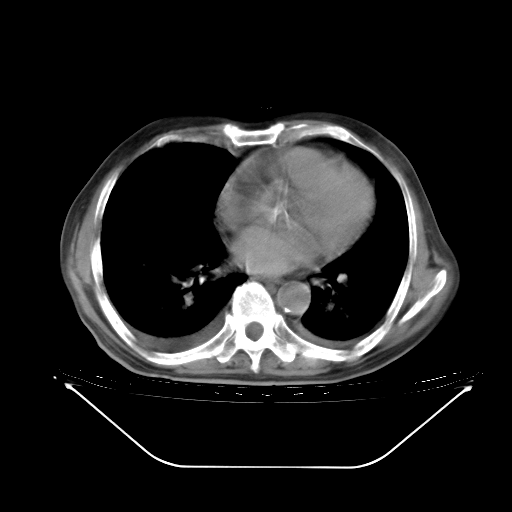

今天复查肺部CT,发现双肺广泛磨玻璃样改变。所以我把3月19日和5月9日相隔50天的肺部CT上传。请大家会诊。

5月9日肺部CT(在4月27日齐鲁医院肺部CT描述部分肺组织磨玻璃样改变,12天后肺组织广泛磨玻璃样改变)

2009年5月9日肺部CT

大致读了系列胸部CT:纵隔窗无明显异常,肺窗:从4、27至今:主要是双肺中下野外带可见毛玻璃样改变,目前处于急性肺泡炎阶段,至于原因考虑1、结替组织或胶原血管性疾病所致?2、恶性疾病如恶组在肺部所致的表现或细支气管肺泡癌?3、药物或其它原因如肺蛋白沉着症所致肺泡炎目前不太可能?总之,明天就去请我院的呼吸科、感染科、血液科和临免专家会诊哈。